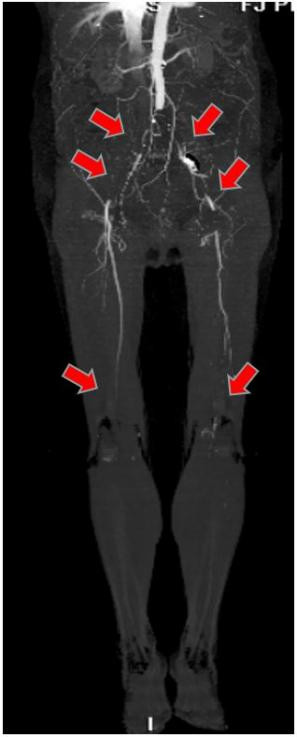

經(jīng)過(guò)CTA證實(shí),伊女士出現(xiàn)的是腹主動(dòng)脈騎跨栓,從腹主動(dòng)脈下段分叉開(kāi)始都出現(xiàn)了不同程度的栓塞,雙下肢出現(xiàn)了嚴(yán)重的缺血。

圖中箭頭所示:術(shù)前CTA提示腹主動(dòng)脈雙髂動(dòng)脈騎跨栓,腹主動(dòng)脈下段及雙髂動(dòng)脈血流中斷